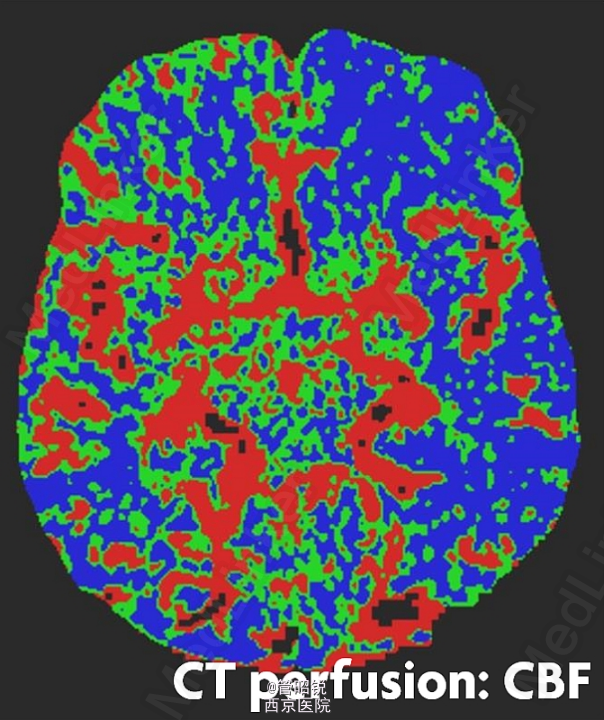

脑室内脑膜瘤占脑膜瘤的0.5%-3%,主要分布在三角区。常发生于中老年女性。原始瘤细胞被认为起源于蛛网膜帽细胞,常常表现为交感神经异常的相关症状,或者症状多变。经典的影像学结果包括CT高密度团块、T2孤立的低信号影、T1WI强化后显示均匀增强。需同转移瘤、淋巴瘤和囊虫病相鉴别。来源于AJNR